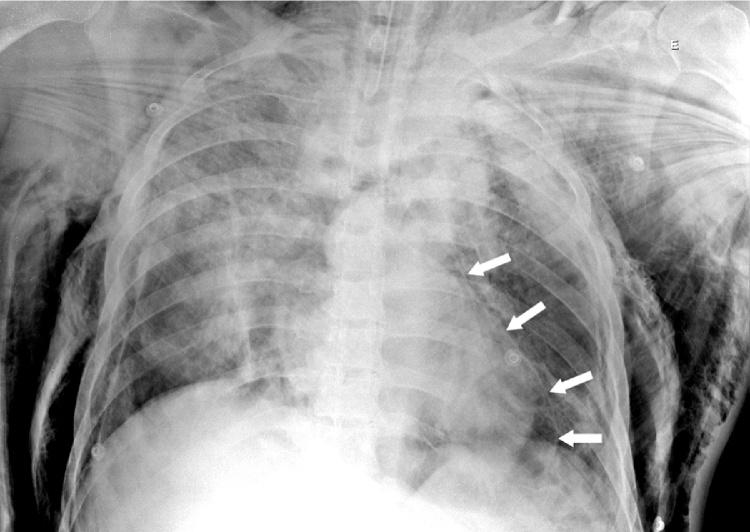

A 51-year-old male was victim of a 4m fall and burial. He was stable upon admission and presented a simple pneumopericardium and pneumomediastinum on CT. While being submitted to an upper digestive endoscopy he presented respiratory failure and had to be intubated, suddenly evolving to shock. He was promptly referred to the operating room; a pericardial window confirmed tension pneumopericardium and immediately hemodynamic stability was restored. A pericardial drain was placed and kept for 15days. He was discharged at the 18th day post-trauma after a satisfactory recovery at the trauma ICU.

Blunt thoracic trauma causes pneumopericardium by various mechanisms. Tension pneumopericardium is a possible outcome, probably related to positive-pressure ventilation. It leads to hemodynamic instability and requires immediate decompression and placement of a pericardial drain.

一名51岁男性从4米高处坠落并被掩埋。入院时情况稳定,CT显示为单纯性心包积气和纵隔积气。在接受上消化道内镜检查时,他出现呼吸衰竭,不得不插管,随后突然发展为休克。他被迅速送往手术室;心包开窗术证实为张力性心包积气,血流动力学立即恢复稳定。放置了心包引流管并保留15天。在创伤重症监护病房恢复良好后,他于创伤后第18天出院。

钝性胸部创伤通过多种机制导致心包积气。张力性心包积气是一种可能的结果,可能与正压通气有关。它会导致血流动力学不稳定,需要立即减压并放置心包引流管。